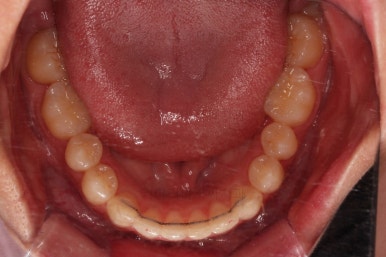

초진 시 입안의 모습이에요.

위아랫니가 모두 삐뚤어요.

특히 앞니가 삐뚤고 위아래 앞니가 고르게 덮여있는게 아니라 뒤죽박죽 엉켜있어서 치아의 마모도 굉장히 많이 되어있는 상태였어요.

치료가 1년만에 종료가 되었네요.

치아가 가지런해졌고, 교합이 잘 맞는 모습이에요.

부산교정 전후사진을 비교해 볼게요.

치열의 모습이 좋아졌고, 웃을 때 보이는 치열이 가지런해서 미소도 훨씬 예뻐졌네요.